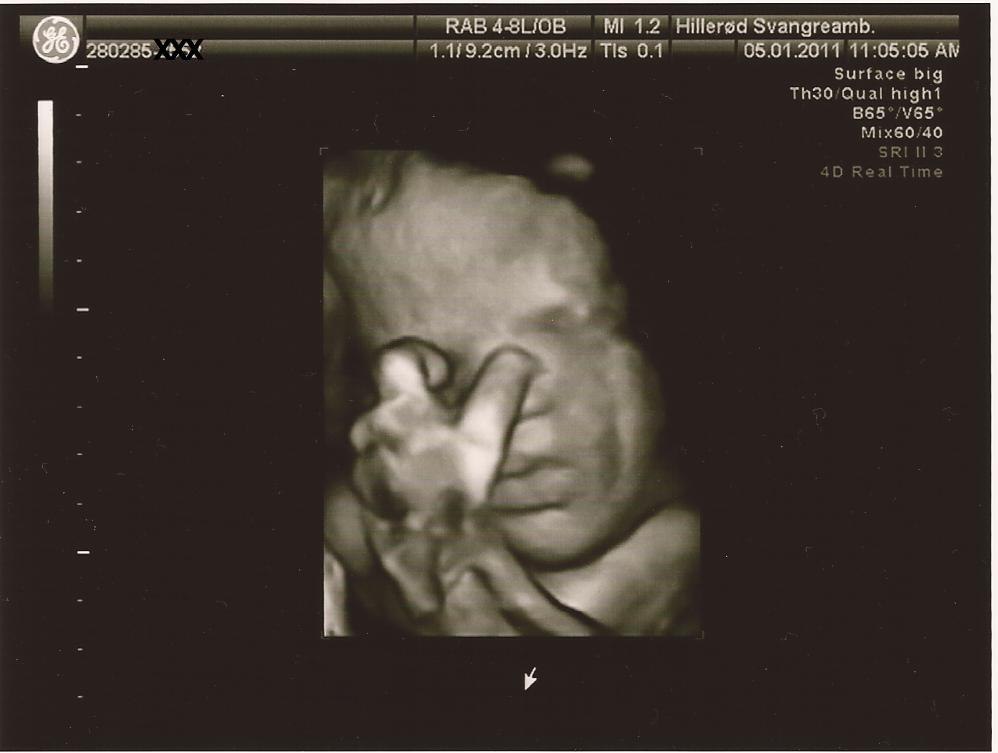

Så er der update. Der var ikke noget at være bekymret for. Med en kampvægt på anslået 2.937 gram er hun 2 % over en absolut gennemsnitsbaby på dette tidspunkt. Dejligt. Og sørme om hun ikke lige slog over i 3D, så vi kunne se at der var sul på kroppen. Det troede jeg ikke de havde mulighed for på det offentlige. Hun var ret overrasket over kvaliteten på 3D, da det normalt ikke er så godt så langt henne i graviditeten. Jeg har desværre ikke mulighed for at ligge billeder ind nu, da vores all-in-one printer er gået i stykker, men har forhåbentlig mulighed for det snart. Hun lignede forresten sin far